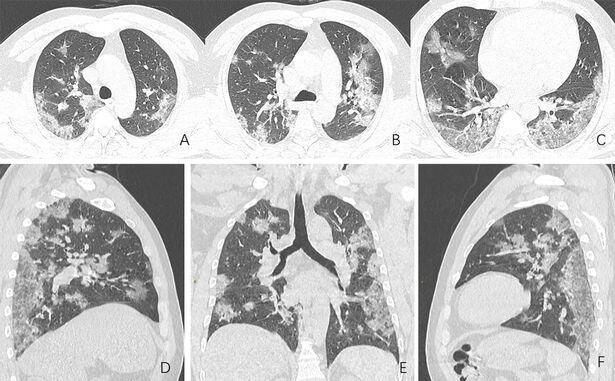

Koronavirus xəstələrinin ağ ciyər müayinəsini əks etdirən rentgen görüntüləri yayılıb.

Oxu24.com metbuat.az-a istinadla xəbər verir ki, koronavirusdan ölən şəxsin rentgen və komputer tamoqrafiya şəkillərində ağ ciyərlərin mərhələ-mərhələ necə məhv olduğu görünür.

Həmin görüntüləri təqdim edirik.